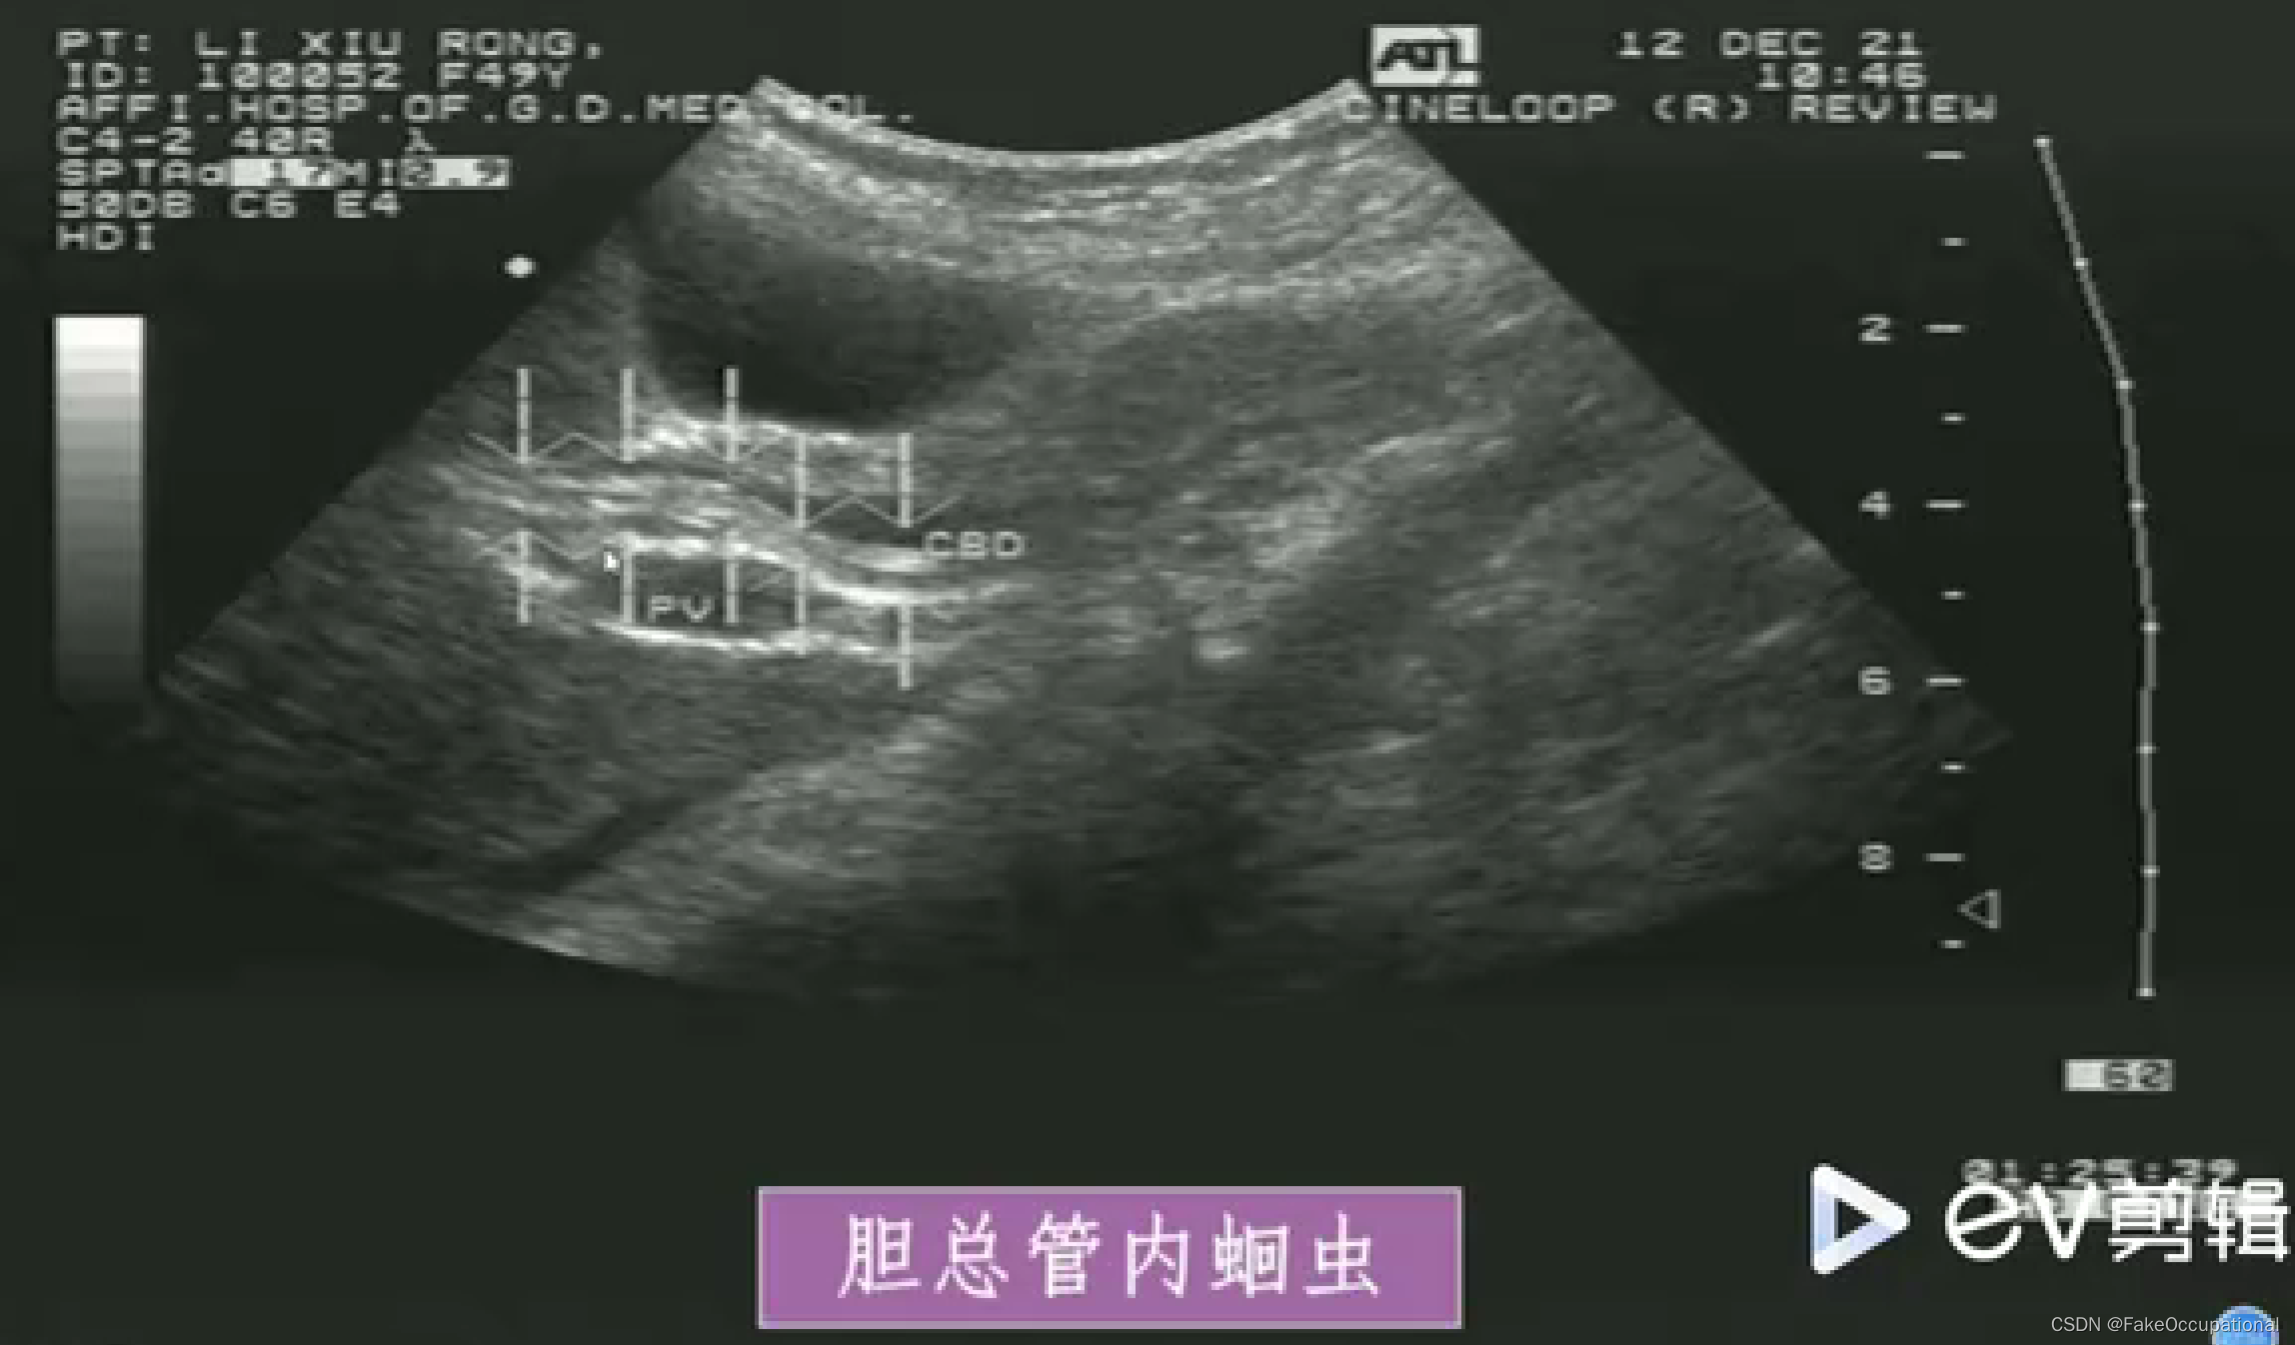

- 扩张胆管内可见蛔虫回纵切面为双线状长条形的平行高回声带,中央可见暗带;黄切面为“同心圆”状

- 活蛔虫可见其蠕动征象具有特异性诊断意义

- 死蛔虫:虫体萎缩,多节段性光带,中央暗带模糊或消失